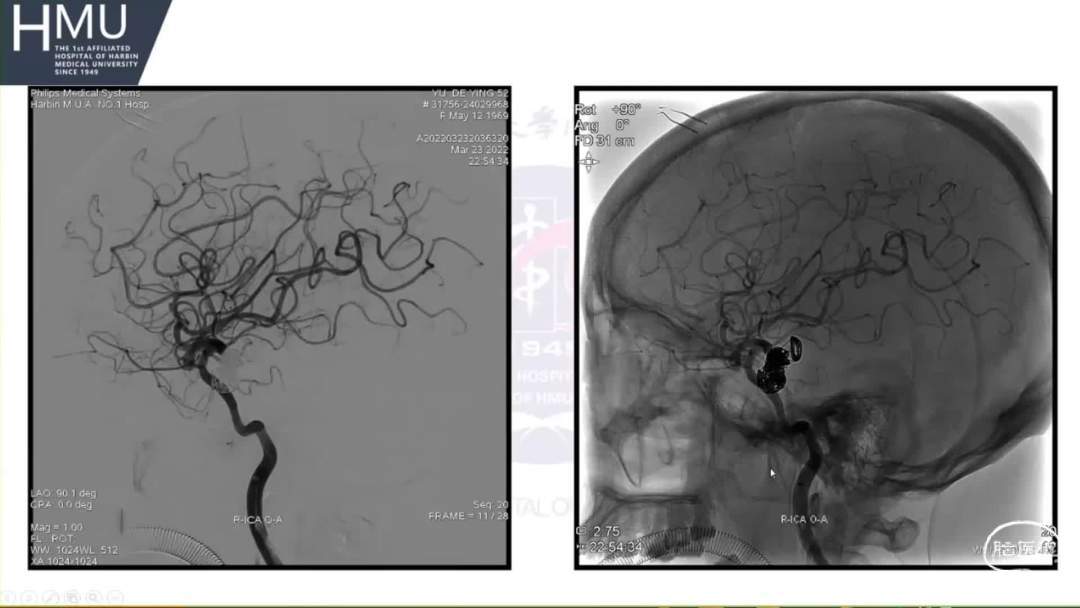

23日06:00

患者答非所问,查体不配合

急行头部CT

23日14:00患者刺痛不睁眼,不发声,

右上肢刺痛定位,左侧瞳孔光反射消失。

16:00急诊行钻孔引流术

21:00覆膜支架置入术